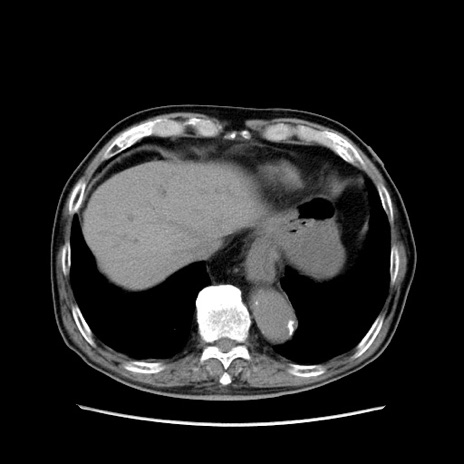

症例24(横断像)

【症例】80歳代男性

【主訴】左側腹部痛、嘔吐

【現病歴】本日早朝より左腹部に痛みあり。昼頃嘔吐認めたため、救急要請。

【既往歴】直腸癌(Mile手術)、胆摘

【身体所見】意識清明、BT 35.9℃、BP 221/93mmHg、SpO2 97%(RA) 、腹部:左ストーマ周囲に限局性の腹部膨隆あり。 膨隆部自発痛・圧痛あり・軟。

【データ】WBC 7700、CRP 0.09